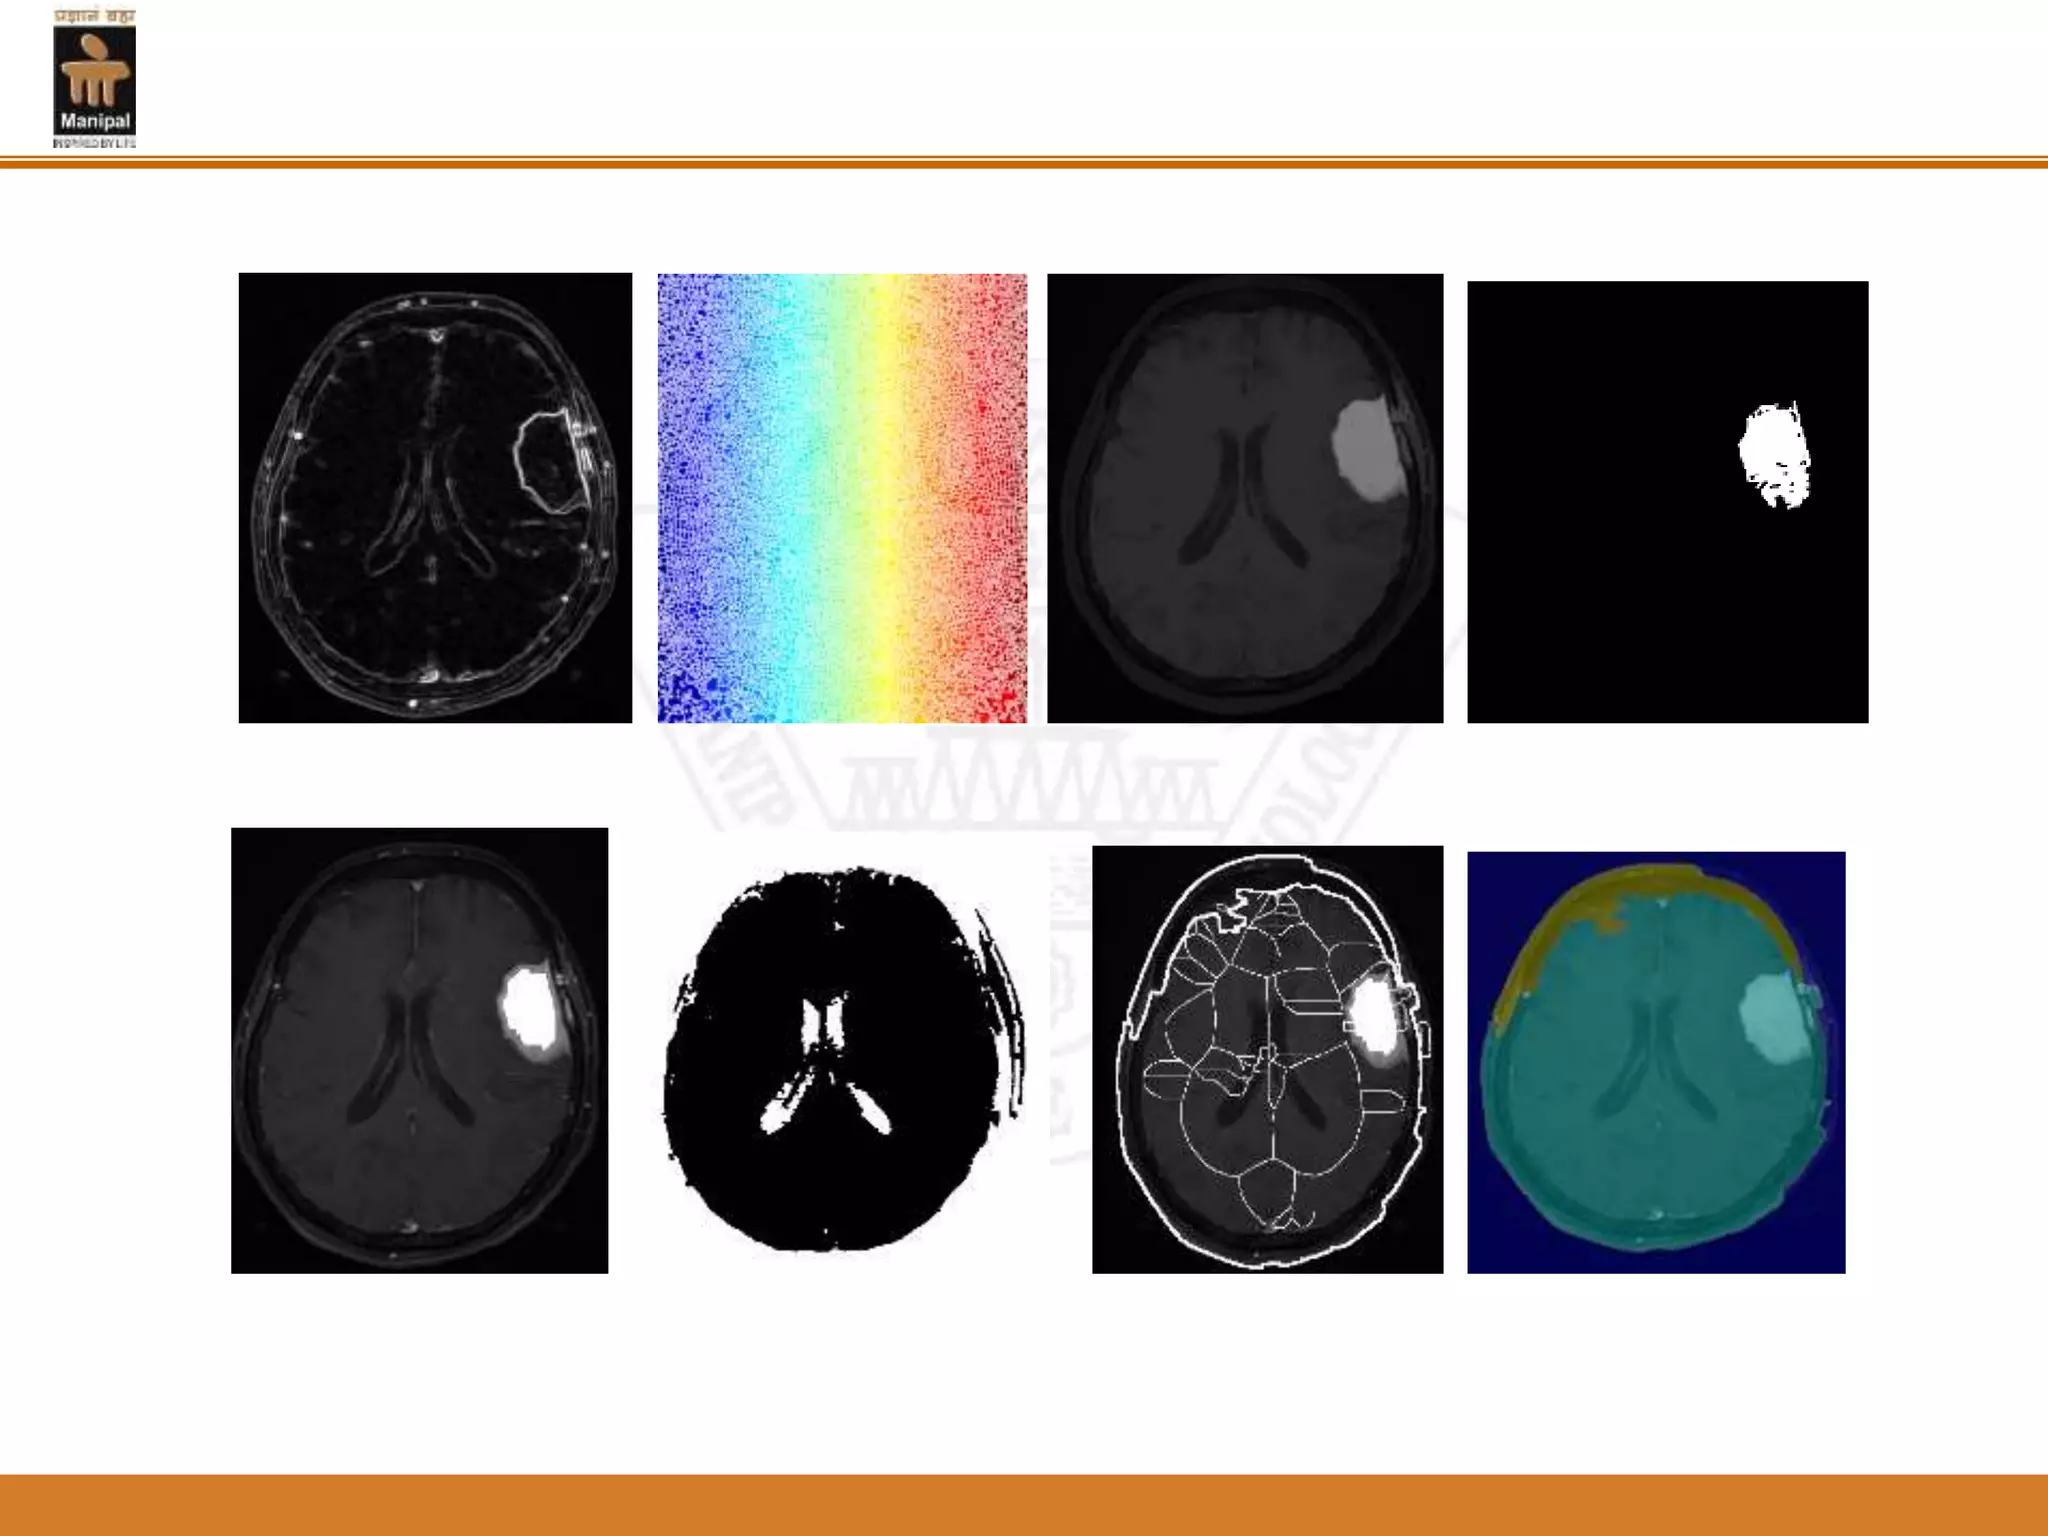

Result analysis

Figure1: Fuzzy C-means clustering (FCM) applied to the MRI

Figure 2: A level set segmentation

Figure 3:The final result

Result analysis Figure1: FuzzyC-means clustering (FCM) applied to the MRI

Figure 2: Alevel set segmentation